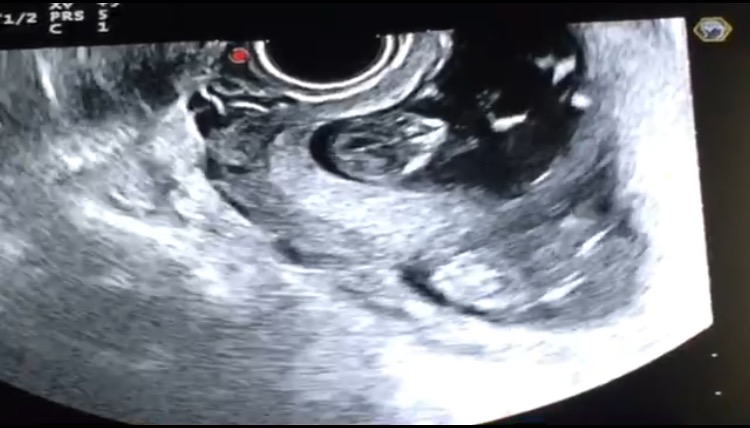

Первый скриринг, 11 недель и 3 дня;).

Всё о нашей беременностиВсем доброго утра, была сегодня на первом скрининге, двойня ди-ди, 11 недель и 3 дня)), как было, дальше....

Наблюдаюсь платно в 4 род. доме, у Николаевой А.В, в жк даже идти не охота, в первую беременность вечно меня пугали, дауна обещали, заставляли прокол делать, я от всего отказалась. Роды закончились конечно трагично, но мой сын был абсолютно здоров ( рожала кстати в Кулакова). Ну не будем о грустном)), и так, принесла 2 банки мочи, экг, взяли мазки, крови 6 пробирок и из пальца))), и самое интересное это УЗИ)))), как я его ждала, но девчонки ждущие и мамочки меня поймут. У нас все хорошо, носы на месте, мозги, руки и ноги), ди-ди у нас, срок по М опережают на 3 дня, по УЗИ 11 недель и 6 дней, смотрели и трансвагинально и через живот, шейка тоже ничего так 35 мм, но врача смотрела меня на кресле, и сказала зашивать точно будет, скорее всего рано на 13 недели, я только за, сказала зашивайте мне там ВСЕ, лишь бы они не вышли раньше времени;)). Шейка у меня рваная после первых родов, нужна подстраховка. В первую беременность все было отлично, даже бандаж не носила, хотя сын родился 4610кг. Результаты скрининга сказали будут к концу недели, но при двойне он не очень супер информативен, но какие то показатели все таки они смотрят)). Следующий приём в понедельник, поверяем шейку)). Настроение прям на подъеме, девочки мечтающие, ждущие, желающие, в положении, все у вас будет, все как вы хотите, главное дождаться этого, не остановиться на пол пути, ещё шаг и счастье в ваших руках;)).

Второго не очень видно)))он под первым лежит, но он тоже скажет во всю)).